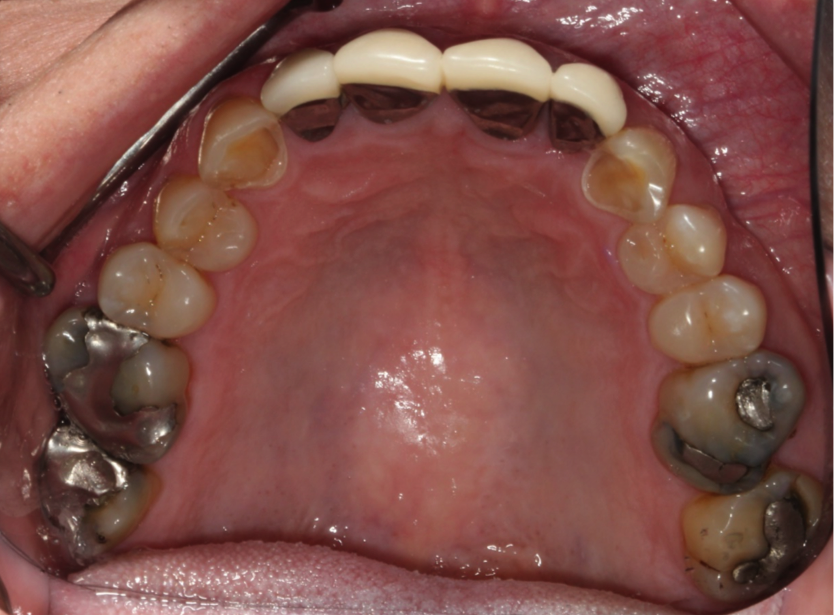

Full mouth of Crowns!

We took a patient that had several worn teeth and restored them back to shape with crowns. We chose metal crowns for this patient because he was a heavy grinder and metal crowns have been shown to be more beneficial than ceramic crowns for patients that grind their teeth.